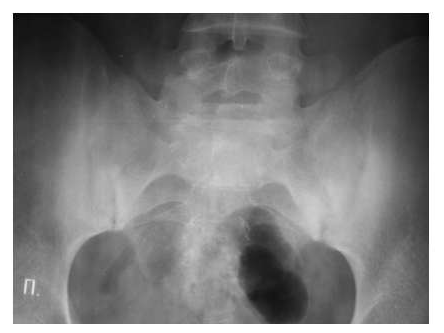

В начальных стадиях (1-2 стадии по Kellgren) ОА тазобедренных суставов при рентгенологическом исследовании определяются: незначительное сужение суставной щели, слабовыраженный субхондральный остеосклероз, точечные кальцификаты в области наружного края крыши вертлужной впадины (зачаток остеофитов), заострение краев ямки бедренной головки в области прикрепления круглой связки бедренной головки (рис. 1).

Рис. 1. Обзорная Rо-графия тазобедренного сустава в прямой проекции.

Деформирующий остеоартроз II ст. по Kollgren. Крупные остеофиты на краях суставных поверхностей. Грибовидная деформация бедренной головки